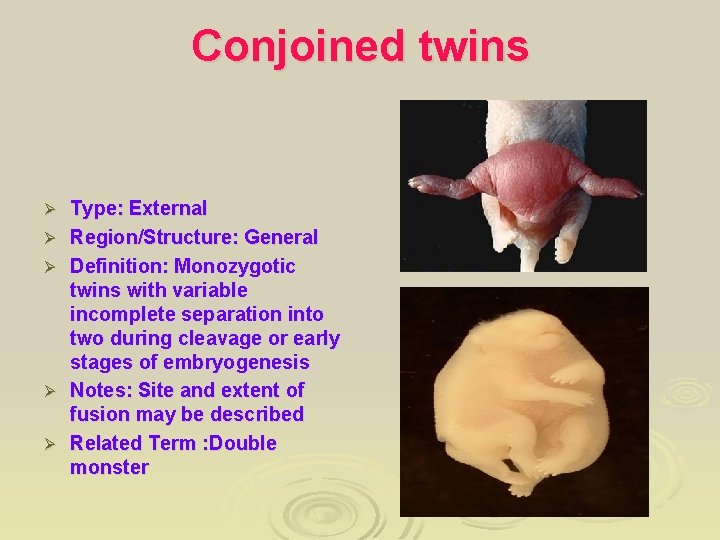

Conjoined twins Ø Ø Ø Type: External Region/Structure: General Definition: Monozygotic twins with variable incomplete separation into two during cleavage or early stages of embryogenesis Notes: Site and extent of fusion may be described Related Term : Double monster